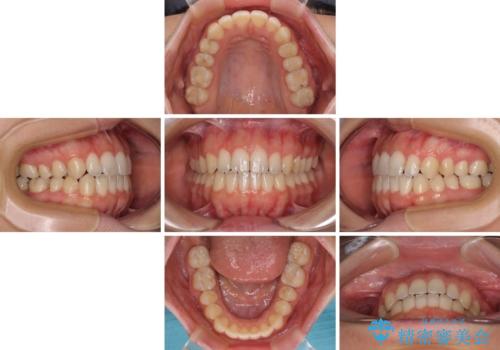

- 前歯の開咬を気にして来院された患者様です。

開咬の治療は、前歯を閉じるように動かすとともに、上下臼歯を圧下(骨内にめり込ませる)させることで進めて行きます。

インビザラインは臼歯の圧下を効果的に行えるため、インビザラインを用いて矯正治療を行うこととしました。

オープンバイトは舌の突出癖により誘発され、治療後も突出癖が残っている容易に後戻りしてしまいます。

治療期間を短縮するためにも、舌突出癖の改善が極めて重要となります。